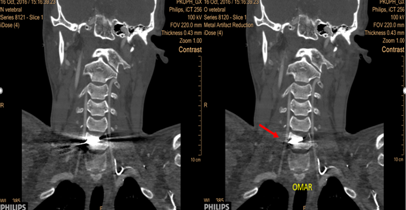

CT: 飞利浦高端CT OMAR去金属伪影技术